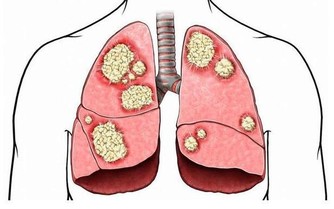

便血不止是痔瘡的常見病症,結直腸癌患者也會出現類似情況,

因此發現大便帶有血跡時,要盡快去醫院確診病因。